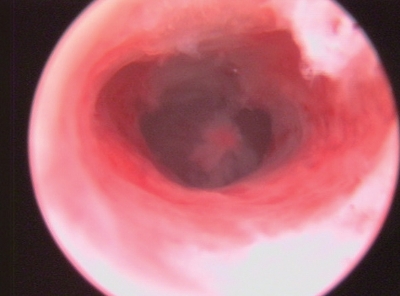

①月经期子宫内膜:内膜剥脱,伴有点状出血,可见部分仍在出血的毛糙小血管。月经干净后整个子宫腔为淡黄红色内膜覆盖,转入增生期(图3-5)。